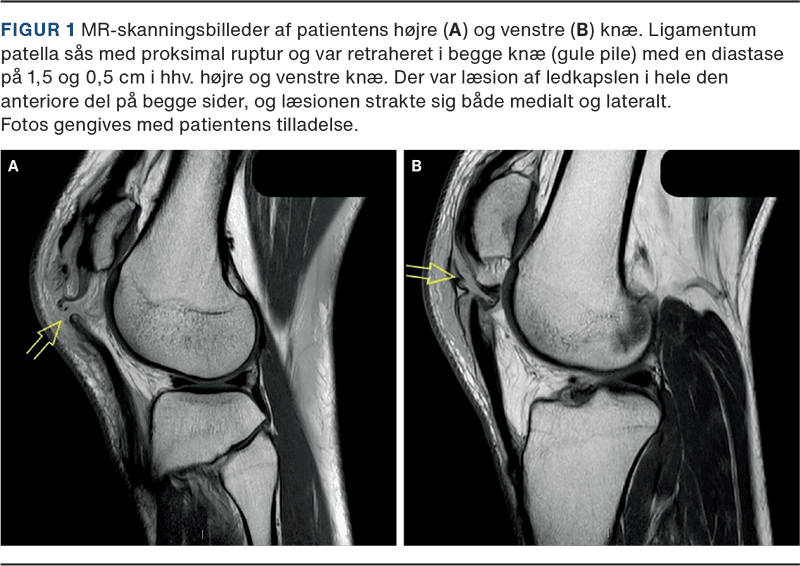

Patienten fik foretaget MR-skanning, som bekræftede PSR og viste påfaldende ens læsioner i anteriore ledkapsel på begge knæ, men ingen andre intraartikulære læsioner (Figur 1). Patienten gennemgik operation af begge knæ på tredjedagen, hvor patellasenen blev sutureret med nonresorberbar sutur ad modum Krakow igennem vertikale borehuller i patella samt metalcerclage fra tuberositas tibiae og omkring patella. Denne metode har vist den laveste risiko for svigt [4], men medfører ofte en sekundær operation med fjernelse af cerclager, hvis de generer, eller ved risiko for, at de knækker. Patienten fik fjernet cerclager fra begge knæ efter ca. fem måneder (Figur 1).

Denne case bidrager til opmærksomhed omkring skader på knæets ekstensorapparat og den diagnostiske tankegang. Patienten var formodentlig prædisponeret, idet han tidligere havde pådraget sig senerupturer ved forskellige skadetidspunkter [3]. I dette tilfælde var der ikke andre intraartikulære læsioner. I et nyligt, systematisk review fandt man 45 dokumenterede tilfælde af samtidig, bilateral PSR, hvoraf kun ti patienter fik foretaget præoperativ MR-skanning. I 18 ud af de 45 tilfælde skete skaden ved sportsaktivitet og i 20 tilfælde ved faldtraumer [2]. Det er altså en sjældenhed at pådrage sig bilateral PSR, og det har ikke været anset som standardpraksis at foretage MR-skanning i denne forbindelse. Turner et al viste, at præoperativ MR-skanning ved skader i ekstensorapparatet (quadriceps- og patellasenen) medførte øget diagnosticering af intraartikulære skader på 50,7%, hvoraf meniskskader var de hyppigste. Af alle ledsagende skader var kun 4,5% kirurgisk behandlingskrævende, men risikoen var højere ved PSR end ved andre ekstensorapparatskader [1]. I denne case var der læsion i anteriore ledkapsel på begge knæ. Selv om dette ikke i sig selv ændrede behandlingen, var det af betydning for operationsplanlægningen at kende til sekundære skader. Med tanke på, at de fleste kan returnere til samme sportsgren, som skaden er sket ved [5], synes det meningsfuldt, at MR-skanning overvejes ved mistanke om PSR.